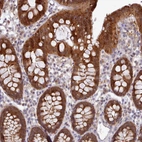

Immunohistochemical staining of human colon shows strong cytoplasmic positivity in glandular cells.